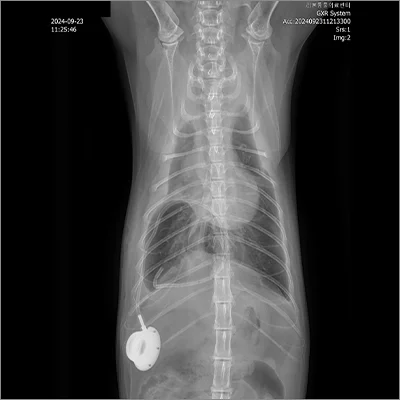

3. 심장사상충 제거술

C-arm 투시 영상장비를 이용해 심장 내부에 기생하는 사상충을 정밀하게 제거합니다

PDA 전

PDA 후